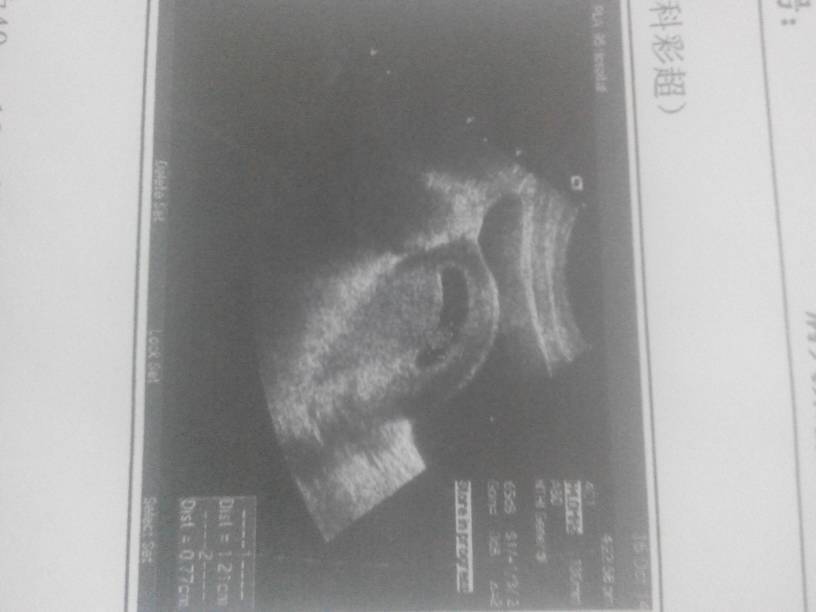

宝妈们帮我看看,我的胎囊正常吗????有拿保胎药回来吃,都吃完好几天了,还没有去产检… 宝妈们帮我看看,我的胎囊正常吗????有拿保胎药回来吃,都吃完好几天了,还没有去产检。。。。 点击展开 简单的过日子 2014-11-07 22:06 为您推荐: 其他回答 那就听医生说怎样就怎样吧 双宝贝 2014-11-08 10:02 多卧床休息,正常 dai 2014-11-08 07:20 应该没事的,不要太担心 魅世紅顏☆丟了芯 2014-11-08 07:14 !!!!! 水灵灵 2014-11-08 06:36 宝妈好运! 有你就很幸福! 2014-11-08 02:18 加载更多 相关问题 我怎么老是见红啊,好了几天又开始了,去医院做B超都是好的 天天吃保胎药啊,有宝妈跟我一样情况的嘛? 那个医生帮我看看正常吗?老是有褐色的分泌物,需要吃保胎药吗? 请问有没有保胎的宝妈 传的经验给我呗